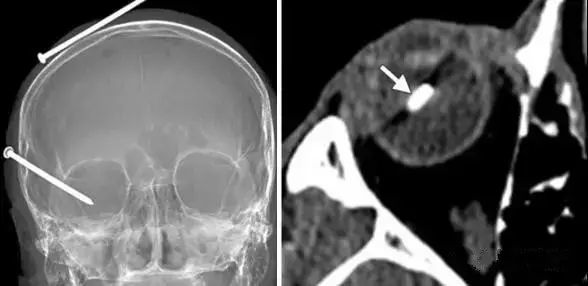

开放性眼球损伤

直接征象:眼球形态和体积异常 , 巩膜不连续;

间接征象:前房深度改变 , 眼球内异物或气体 。